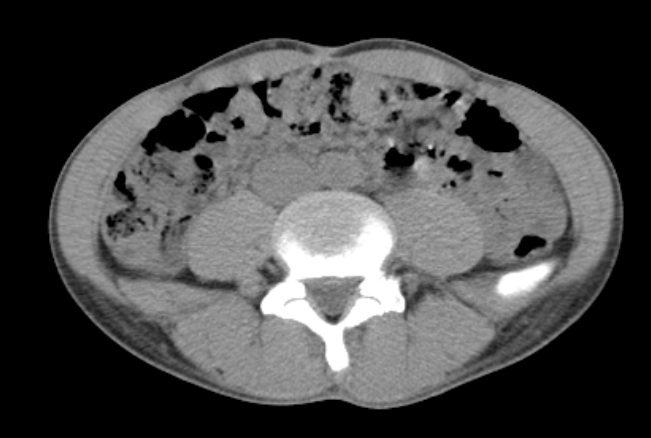

2021/5/13 皮下脂肪4.3mm、後ろ17mm。

だいぶスッキリ。だけど筋肉量も落ちたかな?

内蔵脂肪はかなり減って臓器同士の境目が分かりにくい。

結果、病気があってもはっきりわかりにくくなってしまった。なんだかな〜

画像の内臓の真っ黒は腸内の空気。けっこうう○こがたまっているので、下剤飲めばもっと体重が落とせるとか、ヒルクライム脳なことを思ってみたり。

いちばん脂肪が厚いところは40mm

同じレベル。今回 19mm

ワキバラの肉はなかなか落ちない

けどこれで体脂肪率15%と言われるとツライよGARMIN先生🤔